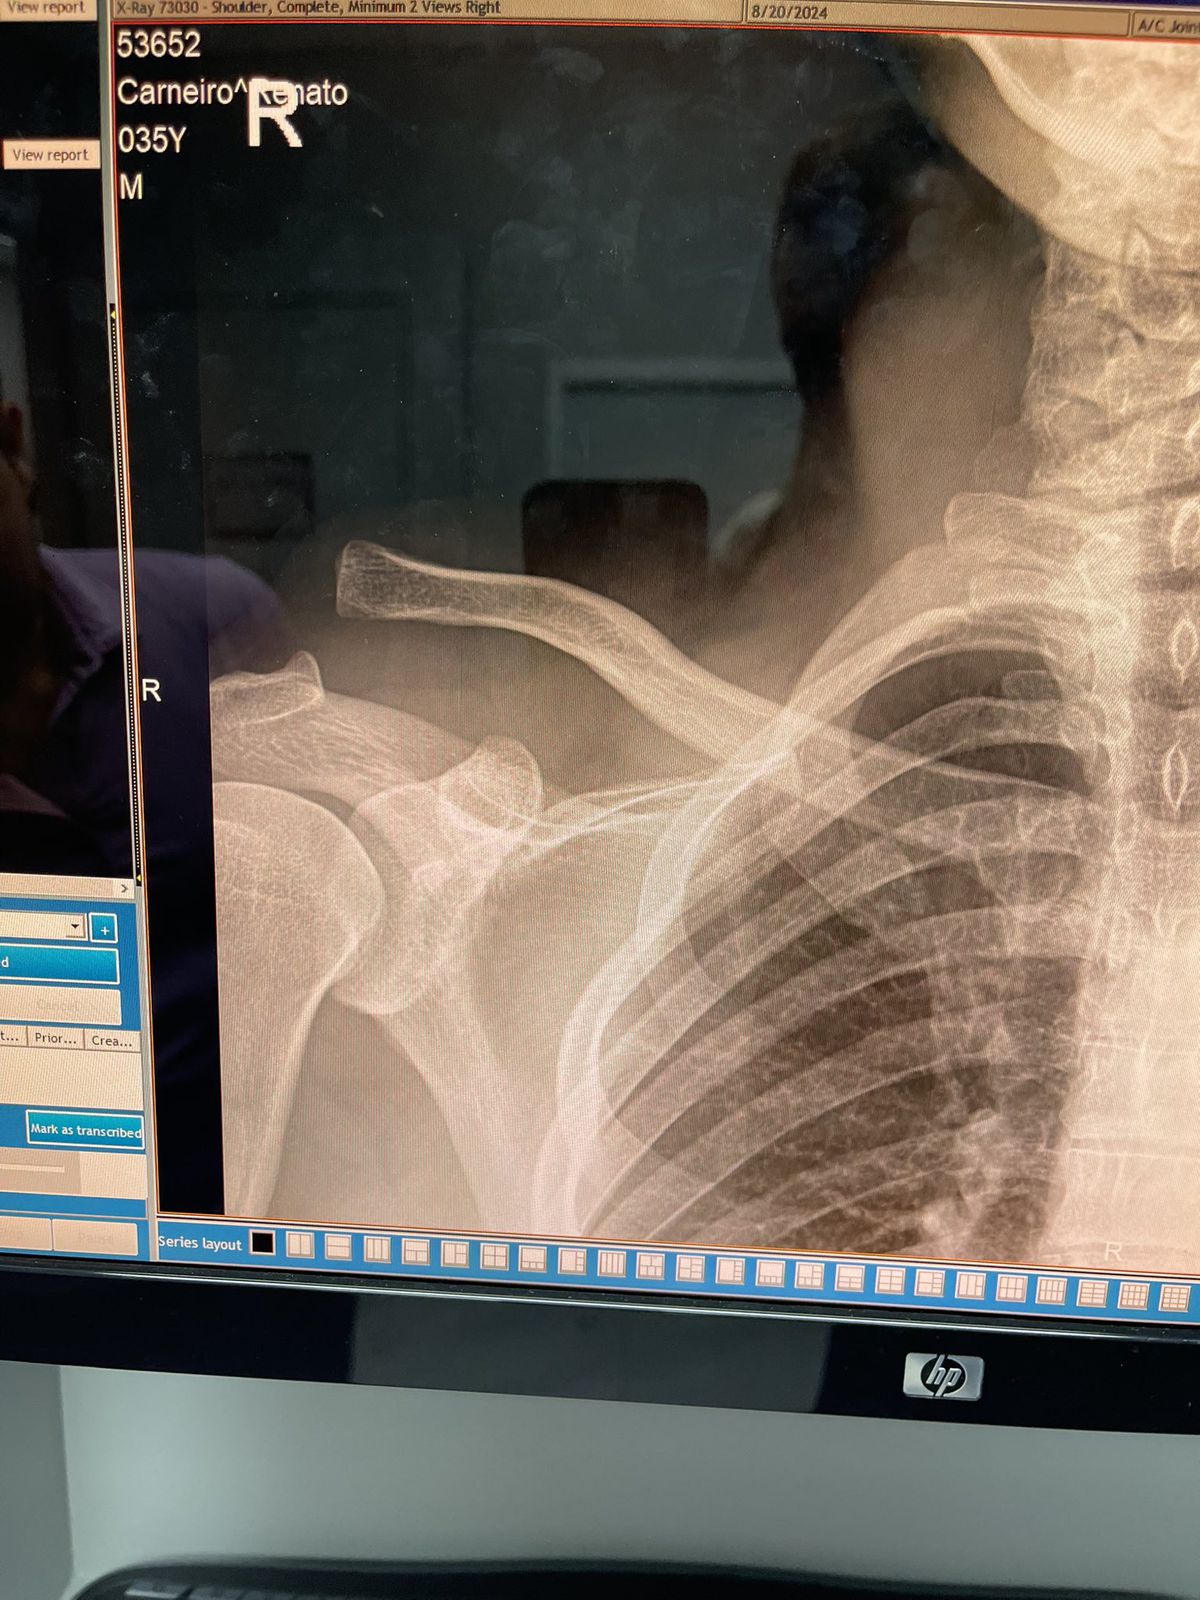

Những bức ảnh chụp X-quang cung cấp cho Kevin Iole cho thấy mức độ chia cắt của vai mà Moicano phải chịu trước trận đấu. Moicano đã chiến đấu vượt qua chấn thương ngay cả khi vai vẫn bị tổn thương trong những khoảnh khắc giao tranh.